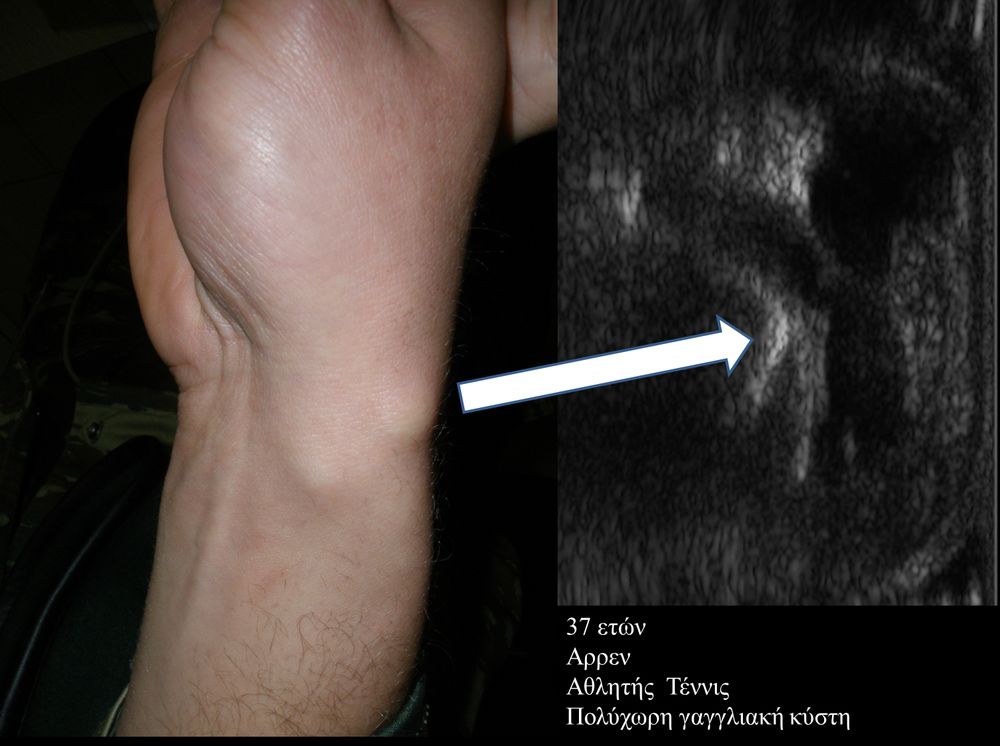

Πρόκειται για υπερηχογράφημα υψηλής ευκρίνειας που επιτρέπει την λεπτομερέστατη απεικόνιση (σε επίπεδο χιλιοστού) ακόμη και πολύ μικρών/επιφανειακών ανατομικών δομών και απαιτεί ειδικό υπερηχογραφικό εξοπλισμό καθώς και εξειδίκευση του ακτινολόγου. Η εξέταση γίνεται με δυναμικό τρόπο, δηλ εκτελούνται δοκιμασίες κίνησης του μέλους που πάσχει, ώστε να αποκαλυφθεί η παθολογίαακόμη και όταν δεν είναι εμφανής σε θέση ηρεμίας. Επιπλέον, η εξέταση είναι ανώδυνη και ασφαλής και δεν περιλαμβάνει ακτινοβολία (CT), μαγνητικό πεδίο (MRI) ή παραμονή σε κλειστό χώρο και είναι πολύ ανεκτή τόσο σε ενήλικες όσο και σε παιδιά.

- Ακρου Ποδός/ Πέλματος (πχ απονευρωσίτιδα)